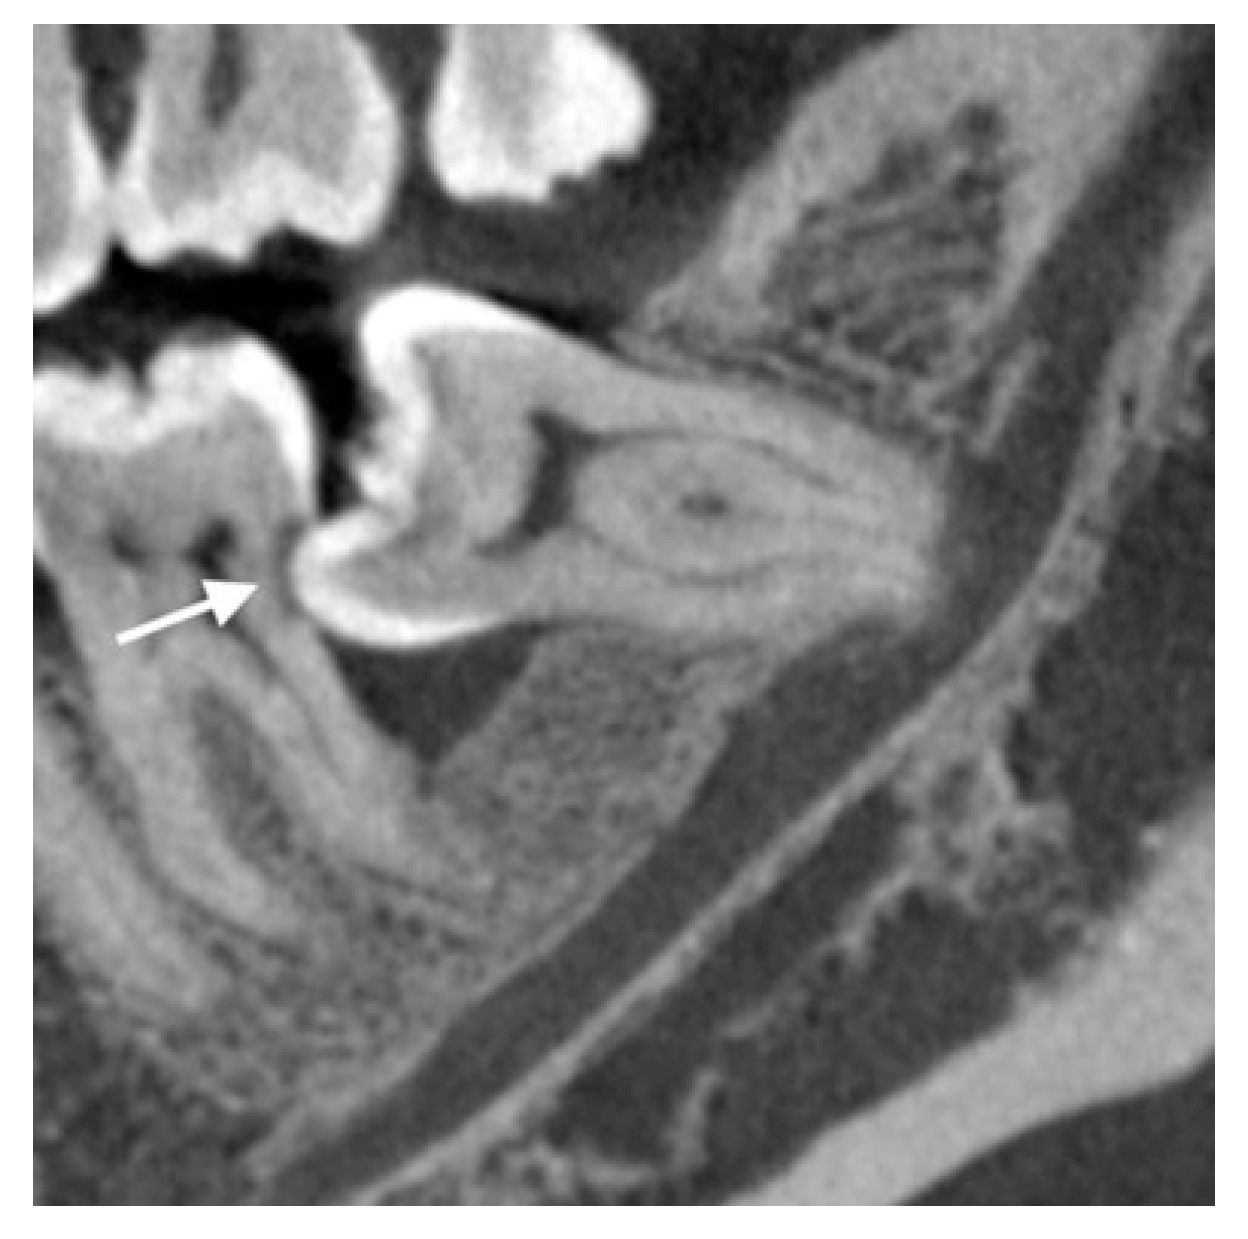

It is known that third molar impaction affects the periodontal health of the adjacent second molar and leads to periodontal attachment loss of the tooth [78]. It is caused by persistent infection because of food trapping and plaque retention, which leads to an inflammatory response and consequential bone and attachment loss. It is important to inform patients with an impacted lower third molar about the prognosis of the adjacent second molar, in particular when there is advanced periodontal bone loss at the distal aspect of the tooth. Removal of the impacted third molar is a treatment of the condition, but the periodontal pocket may persist, especially when there is severe localised bone loss pre-operatively. The dilemma of considering whether to remove the lower third molar or not is often the reason for the procrastination of the treatment. One study found an average of 5.7 mm pocket at the distal aspect of the second molar at nine years post-third molar surgery if there was no adjunctive periodontal treatment [79]. Older age was found to be a risk factor for the residual periodontal pocket. Kugelberg noted that over 25% of patients older than 25 years had a residual pocket of over 7 mm at the distal aspect of the second molar 2 years after the surgery [80]. A recent systematic review and meta-analysis showed baseline periodontal probing depth was strongly correlated with final periodontal probing depth [81]. When the pre-operative periodontal bone loss is too advanced, the long-term prognosis of the second molar could be jeopardized even when the causative third molar is removed. As part of the risk assessment and informed consent procedure of the third molar surgery, the clinician should discuss the fate of the adjacent second molar, considering the amount of periodontal bone loss prior to the surgery. While OPG is usually sufficient as an assessment imaging for many third molar surgery cases, CBCT allows accurate 3D evaluation of the pre-operative and post-operative bone level of the second molar (Figure 3). Dias et al. found that for the same sample of cases with impacted lower third molars, CBCT could detect 80% of the cases with marginal bone loss, while OPG could only detect 62.9% [82]. For post-operative periodontal healing of the second molar, a recent CBCT study on lower third molar coronectomy showed an increase in the bone level at the distal aspect of the second molar ranging from 3.2 mm to 3.5 mm in the long-term follow-up [53]. When extensive bone loss is noticed, guided bone regeneration on the second molar may be performed together with the third molar surgery to improve the periodontal attachment of the tooth [54,81]. With the information from the CBCT, the clinician could inform the patient on the periodontal condition of the second molar, the estimation of its long-term prognosis, as well as treatment alternatives or adjunctive treatment required before and after the lower third molar surgery.

Figure 3.

Representative CBCT image showing bone loss at the distal of a left lower second molar with root resorption (white arrow) caused by a mesioangular impacted third molar.